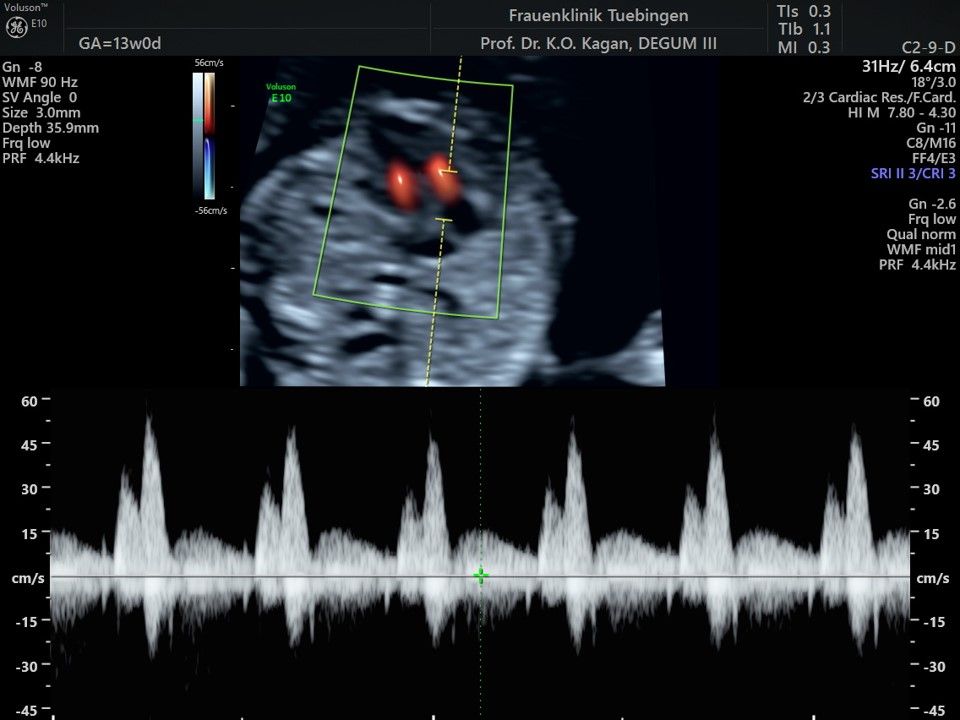

Herz

Das Ergebnis der Ultraschalluntersuchung ist wegweisend. Dabei wird der Fet vermessen, die Organe werden untersucht und die sonographischen Marker zur Risikoberechnung für Chromosomenstörungen werden beurteilt. Das sind: die Nackentransparenzdicke, Nasenbein sowie der Blutfluss in der rechten Herzhälfte und im Ductus venosus, einem Gefäß in der Leber des Feten.